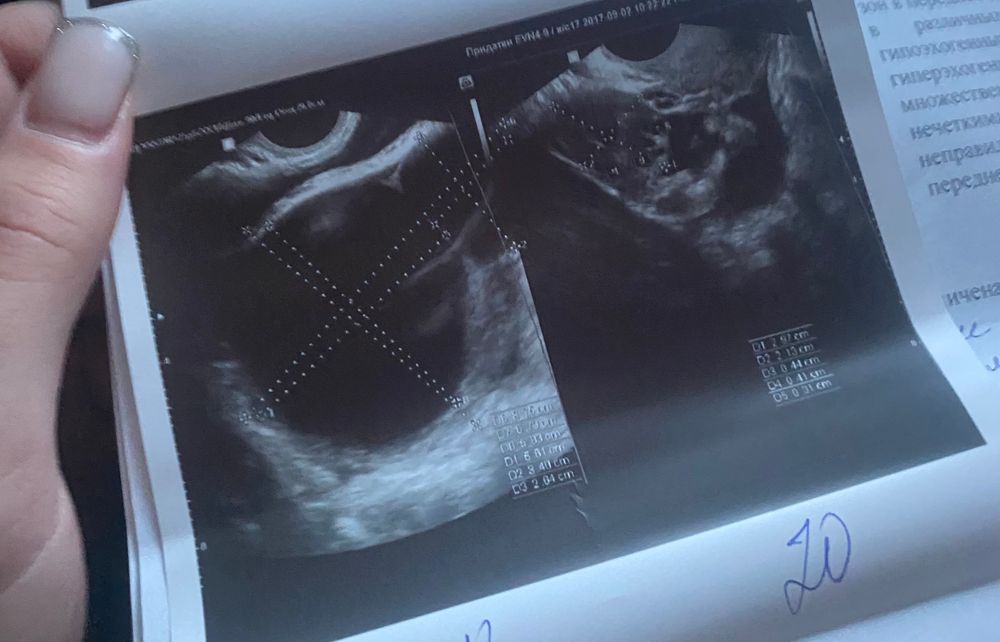

я беременна, но есть киста которая за 10 дней выросла в 2 раза, она большая, мне страшно что она может повлиять на беременность, лопнуть или еще что, была у врача сказала если не болит не переживаем, чтобы оперировать срок беременности маленький, у кого была киста во время беременности?

У меня была киста ЖТ где-то 8*6. Врач прав, просто ведите себя аккуратно) Половой и физический покой.